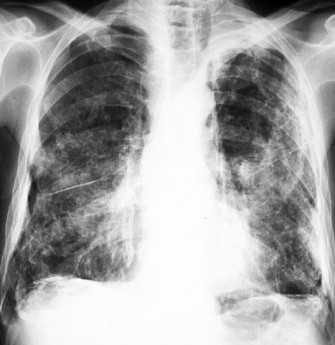

• Asbestose

L'asbestose, une affection pulmonaire grave, touche les personnes qui ont inhalé de la poussière d'amiante. Après l'inhalation de cette poussière, les fibres d'amiante microscopiques se déposent dans...